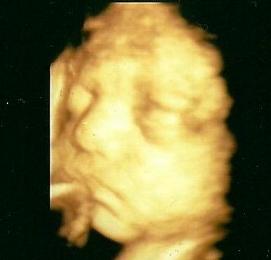

Na, és akkor jöjjön a durci Bendegúz :-D folyton az arca elé kapkodta a kezeit, és dacosan összeszorította a száját, nem tetszett neki :-)

Kép Kép

Amúgy minden rendben vele, műxik rendesen, 1054 grammosnak saccolta a gép :lol: